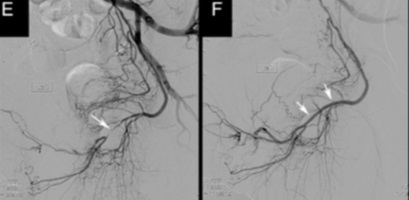

Il nostro gruppo a messo a punto un protocollo di studio dei pazienti affetti con disfunzione erettile, che prevede lo studio della stessa attraverso un ecoDoppler dinamico con iniezione di prostaglandine sulla base del pene, seguito da un angioTAC in caso di positività e la somministrazione al paziente di 5 mg di Cialis in cronico con osservazione di almeno 1 mese. I pazienti con stenosi accertata e non responività agli inibitori delle fosfodiesterasi vengono inviati alla procedura di angioplastica percutanea che effettuiamo non con stent ma con palloni a rilascio di farmaco che a nostro avviso trovano maggiori indicazioni in questi segmenti di vasi di piccolo calibro.